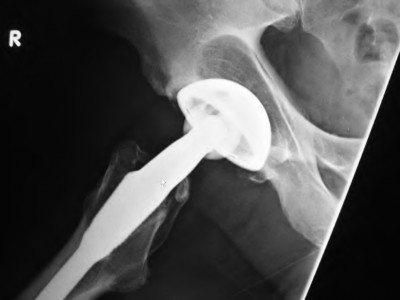

A 72-year-old male presents 2 years status post fixation of an impending pathologic right femur fracture due to metastatic renal cell carcinoma. He is minimally ambulatory due to pain. Despite radiation therapy, there has been progression of the lesion with extensive cortical bone loss, which is shown in Figure A. A proximal femoral replacement arthroplasty is performed without complications, and is demonstrated in Figure B. Which of the following is true regarding this patients post-operative course?

Deep prosthetic infection is the most common complication after hip arthroplasty performed for salvage of failed internal fixation after pathologic proximal femoral fracture secondary to malignancy.

Jacofsky et al reviewed the complications in 42 patients with a mean age of 63 who were treated with hip arthroplasty for salvage of failed treatment of a pathologic proximal femoral fracture. Multiple different constructs were used.

The most common complication was deep prosthetic infection, which occurred in nearly 10% of the patients studied. All infections occured in patients whom had previously received radiation. The mean Harris Hip score improved from 42 to 83 points post-operatively, and 41 of the 42 patients were ambulatory at follow-up. Implant survivorship free of revision for any reason at 5 years was 90%, and free of revision for aseptic failure or radiographic failure was 97%.

Figure A shows a lytic lesion of the proximal femur with an intramedullary implant. Figure B shows a proximal femoral replacement.